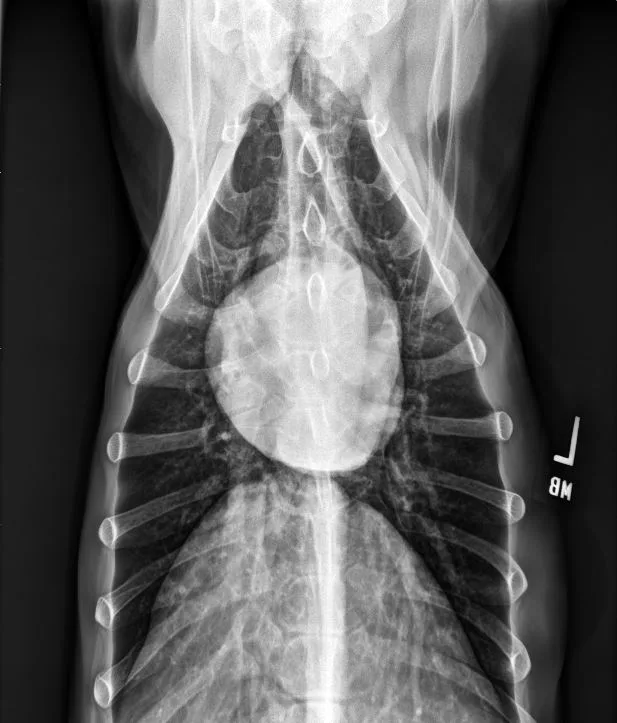

FIGURE 11 Right lateral (left) and VD (right) projections of a crossbreed dog with tricuspid valve dysplasia. The cardiac silhouette has increased width, and the regions of the right atrium and ventricle show roundness. The cardiac apex is displaced to the left secondary to right-sided enlargement (right). The caudal vena cava (arrowheads) is dilated, and there is loss of abdominal serosal detail secondary to increased systemic venous pressures and right-sided CHF, respectively. The pulmonary vasculature is small secondary to pulmonary hypoperfusion (given significant regurgitation across the tricuspid valve and decreased forward blood flow). VHS, VLAS, M-VLAS, and VRHi collected from the right lateral view are 12.3, 2.3, 2.7, and 3.8, respectively. Images courtesy of Bruna Del Nero, DACVIM (Cardiology)